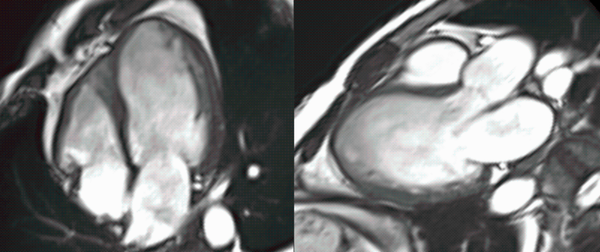

Non-Ischemic Cardiomyopathy

A common clinical presentation of LBBB induced cardiomyopathy is described in this post. It is always dilemma that if LBBB is cause or effect of dilated cardiomyopathy. However CMR can help in differentiating it from other causes and also in predicting response to device therapy. Utilise CMR to the fullest.